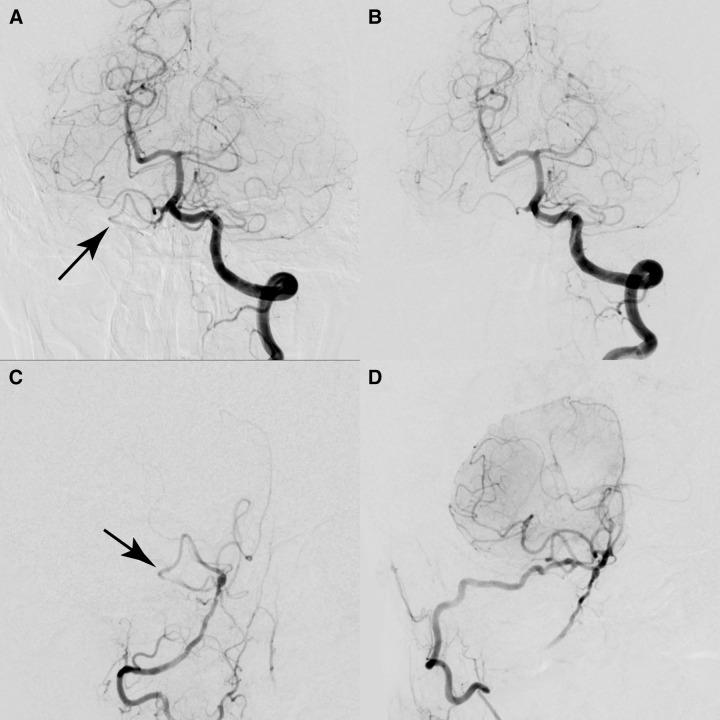

Exertional vertebrobasilar insufficiency (VBI) secondary to the non-atherosclerotic cause is uncommon. We herein report the case of a patient who developed exertional VBI long after extracranial right vertebral artery (VA) dissection. At the time of dissection, the right VA was completely occluded near its origin, but the distal flow was compensated by the collateral flow from the right deep cervical artery (DCA). After conservative management, the patient was discharged without neurologic deficit. Six years later, he developed recurrent VBI in association with the exertion of his right shoulder. A vascular evaluation revealed that the right proximal VA was still occluded, and there was no evidence of right subclavian artery lesions. The intracranial right VA flow was markedly reduced during the period, while branches of the right DCA were given off to the muscles of the right shoulder and neck. Then, occipital artery (OA)-posterior inferior cerebellar artery (PICA) anastomosis was performed. Intraoperative indocyanine green videoangiography (ICG) confirmed that the flow of the right PICA was predominantly supplied from the compensatory flow from the contralateral VA, and the antegrade flow in the right VA was clearly delayed in comparison to that of the left VA while there were prominent branches providing the blood flow to the medulla oblongata. After the anastomosis, these medullary branches provided the blood flow to the medulla oblongata more quickly and extensively than before. Postoperatively, VBI no longer occurred even after exertion. Surgical revascularization can be a viable option in the treatment of refractory VBI of the non-atherosclerotic cause.

非动脉粥样硬化性病因继发的劳力性椎基底动脉供血不足(VBI)并不常见。我们在此报告一例患者,其在右侧颅外椎动脉(VA)夹层形成很久后出现劳力性VBI。夹层形成时,右侧VA在其起源处附近完全闭塞,但远端血流由右侧颈深动脉(DCA)的侧支循环代偿。经过保守治疗,患者出院时无神经功能缺损。六年后,他在右侧肩部用力时出现复发性VBI。血管评估显示右侧近端VA仍闭塞,且无右侧锁骨下动脉病变的证据。在此期间,右侧颅内VA血流明显减少,而右侧DCA的分支分布于右侧肩部和颈部肌肉。然后,进行了枕动脉(OA)-小脑后下动脉(PICA)吻合术。术中吲哚菁绿视频血管造影(ICG)证实,右侧PICA的血流主要由对侧VA的代偿血流供应,与左侧VA相比,右侧VA的顺行血流明显延迟,同时有突出的分支为延髓提供血流。吻合术后,这些延髓分支比以前更快、更广泛地为延髓提供血流。术后,即使在用力后也不再发生VBI。手术血运重建可能是治疗非动脉粥样硬化性病因所致难治性VBI的可行选择。